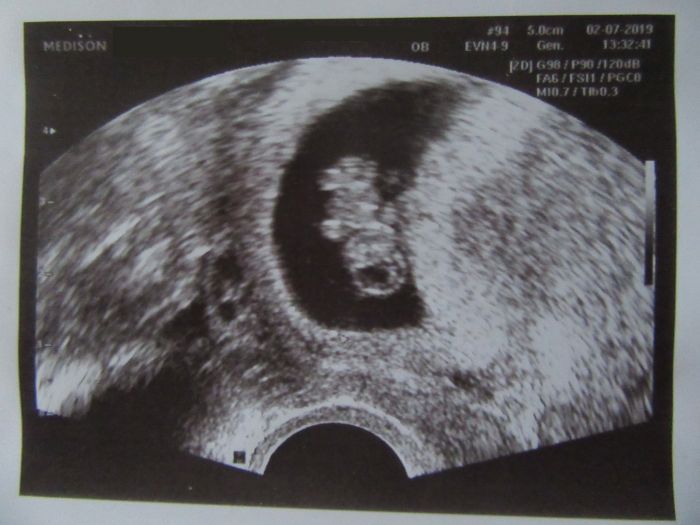

jinak dle velikosti plodu dnes 8+6, TP 6.2.2020. Už máte některá fotku z UTZ?